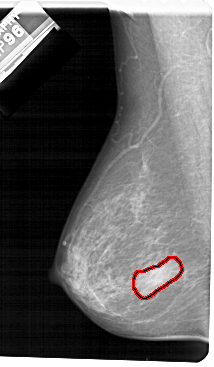

A_1483_1.LEFT_CC

LEFT_CC LINES 5491 PIXELS_PER_LINE 2926 BITS_PER_PIXEL 12 RESOLUTION 43.5 OVERLAY

FILE: A_1483_1.LEFT_CC.OVERLAY

TOTAL_ABNORMALITIES 1

ABNORMALITY 1

LESION_TYPE MASS SHAPE IRREGULAR MARGINS ILL_DEFINED

ASSESSMENT 4

SUBTLETY 5

PATHOLOGY BENIGN

TOTAL_OUTLINES 1

BOUNDARY